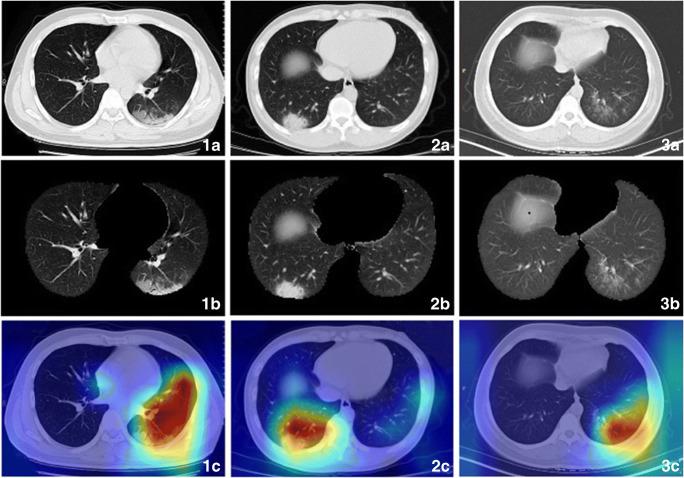

• In an internal validation set, our DL model achieved the best performance to differentiate COVID-19 from non-COVID-19 pneumonia with a sensitivity of 0.836, a specificity of 0.800, and an AUC of 0.906 (95% CI: 0.886-0.913) when the threshold was set at 0.685. • In the prospective RWD cohort, our DL diagnostic model achieved a sensitivity of 0.811, a specificity of 0.822, and AUC of 0.868 (95% CI: 0.851-0.876), non-inferior to the performance of 3 experienced radiologists. • The attention heatmaps were fully generated by the model without additional manual annotation and the attention regions were highly aligned with the ROIs acquired by human radiologists for diagnosis.

• 在内部验证集中,当阈值设定为0.685时,我们的DL模型在区分COVID-19和非COVID-19肺炎方面表现最佳,敏感性为0.836,特异性为0.800,AUC为0.906(95%CI:0.886-0.913)。• 在前瞻性真实世界数据集队列中,我们的DL诊断模型敏感性为0.811,特异性为0.822,AUC为0.868(95%CI:0.851-0.876),不劣于3名经验丰富的放射科医生的表现。• 注意力热图完全由模型生成,无需额外手动标注,且注意力区域与人类放射科医生用于诊断的感兴趣区域高度对齐。